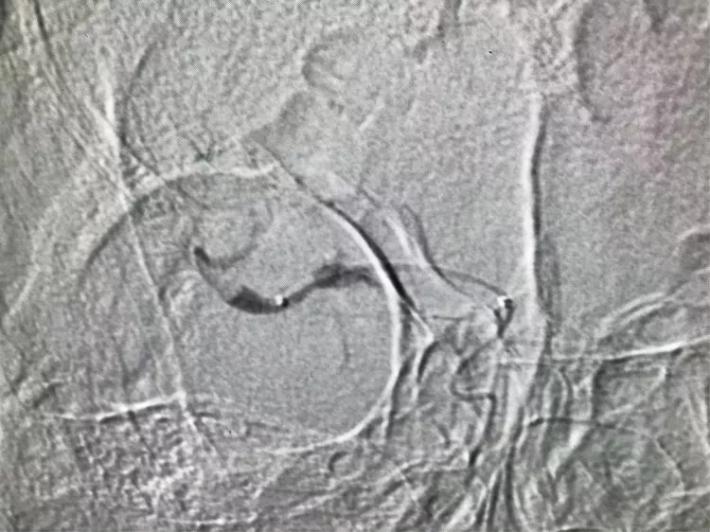

桥接动脉取栓,造影显示:基底动脉闭塞。

微导管进入基底动脉尖部,显示进入真腔。

置入支架,见基底动脉有血流。

取出支架,血管闭塞。

第二次上微导管进入真腔。

置入支架,基底动脉有血流。

取出支架,血管未开通。

第三次上微导管。

支架打开取栓。

见基底动脉血流恢复,左侧大脑后动脉血流欠佳。